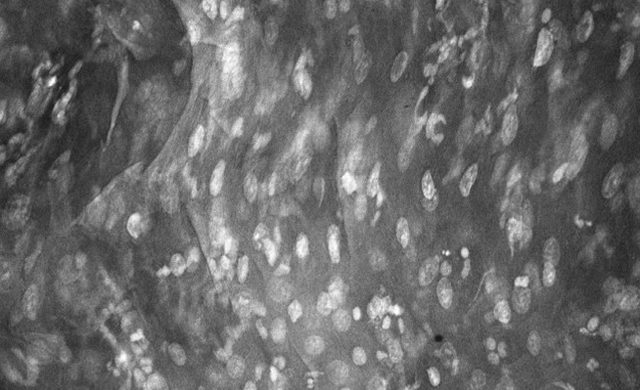

InVivage® is an intra-oral digital endomicroscope that offers the power of single-cell oral imaging at your fingertips. InVivage® by Optiscan is built with our unique patented 3D imaging technology, providing live microscopic oral imaging solutions in optimal resolution, and unlimited image capture to assist in immediate informed decision making.

- Optimized for imaging cellular architecture, in clinical and research settings, at single cell level

- Produces real-time, high-resolution images at 1000x real magnification

- Images easily interpreted using recognized WHO diagnostic criteria for oral epithelial dysplasia

InVivage® can help clinicians distinguish normal, precancerous and cancerous oral tissue.